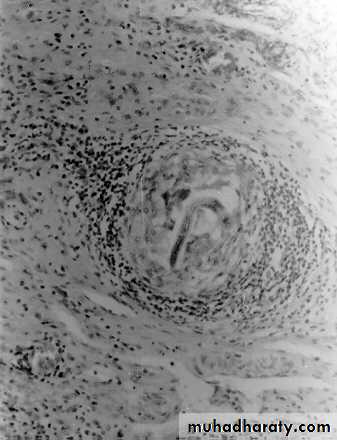

Pulmonary granuloma